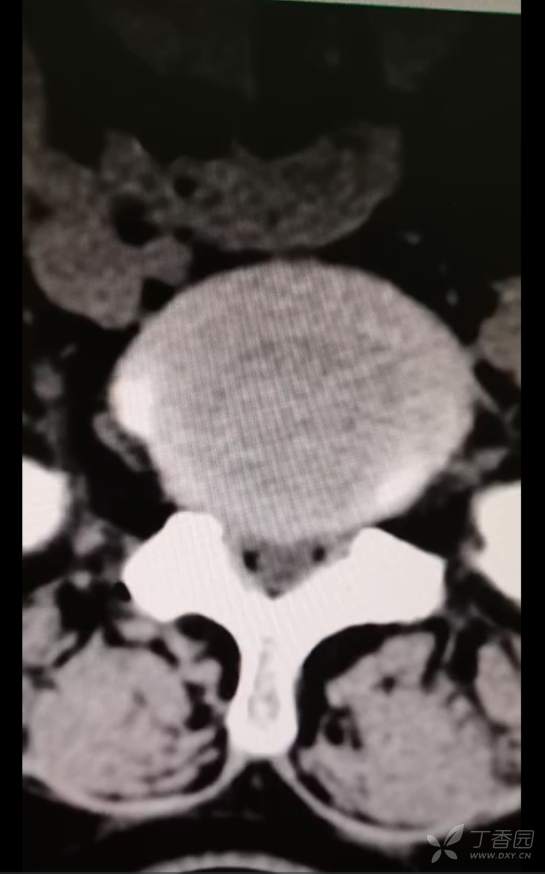

黄骨头脊柱内镜——腰4-5椎管狭窄侧路减压一例